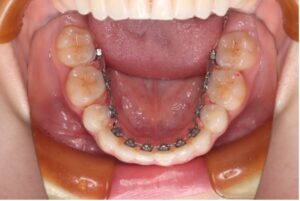

上下ともブラケットを裏側につける、もっとも見えないワイヤー矯正です。

正面からはほぼ見えないため審美性を重視したい方にはメリットが大きい矯正方法ですが、これまでの矯正装置の中で一番舌に当たりやすいため、発音がしづらく慣れるまでは強い違和感があります。また、料金も一番高価です。

〈メリット〉

・装置がほとんど見えない

・見た目を気にせずに矯正治療ができる

〈デメリット〉

・舌に違和感が出やすい

・話すのに慣れるまで時間がかかる

・費用が他に比べると高くなる

・装置が裏側についているため歯磨きがしづらい